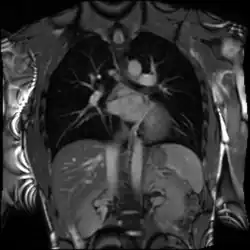

Cardiac magnetic resonance imaging (cardiac MRI, CMR), also known as cardiovascular MRI, is a magnetic resonance imaging (MRI) technology used for non-invasive assessment of the function and structure of the cardiovascular system.[2] Conditions in which it is performed include congenital heart disease, cardiomyopathies and valvular heart disease, diseases of the aorta such as dissection, aneurysm and coarctation, coronary heart disease. It can also be used to look at pulmonary veins.[3]

Cardiovascular MRI is complementary to other imaging techniques, such as echocardiography, cardiac CT, and nuclear medicine. The technique has a key role in evidence-based diagnosis and treatment of cardiovascular disease.[4] Its applications include assessment of myocardial ischemia and viability, cardiomyopathies, myocarditis, iron overload, vascular diseases, and congenital heart disease.[5] It is the reference standard for the assessment of cardiac structure and function,[6] and is valuable for diagnosis and surgical planning in complex congenital heart disease.[7]

Combined with vasodilator stress, it has a role in detecting and characterizing myocardial ischemia due to disease affecting the epicardial vessels and microvasculature. Late gadolinium enhancement (LGE) and T1 mapping allow infarction and fibrosis to be identified for characterizing cardiomyopathy and assessing viability.[8] Magnetic resonance angiography may be performed with or without contrast medium and is used to assess congenital or acquired abnormalities of the coronary arteries and great vessels.[9]